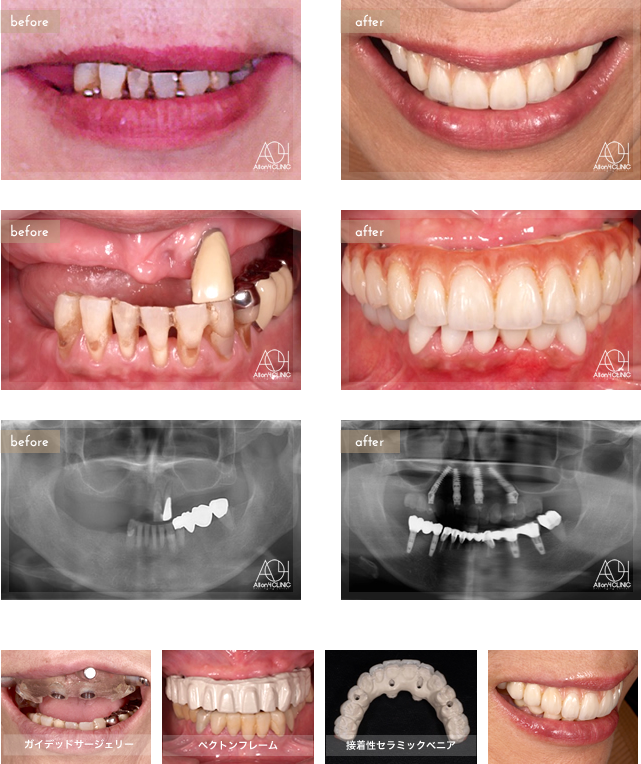

Age : 69

Sex : Female

Treatment : 2013

-Maxilla All-on-4

- Under -

Age : 61

Treatment :

- Maxilla All-on-4

- Under All-on-4

上顎は4本のNobel Activeインプラントを埋入。上顎上部構造はペクトンフレーム(歯肉:アクリリックレジン 歯:接着性セラミックベニア)